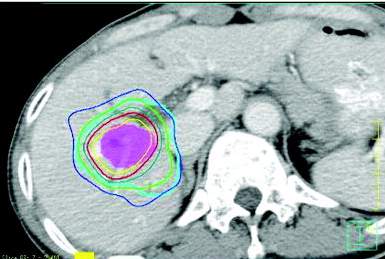

| Technologic advances have

provided the means to deliver tumoricidal doses of radiation therapy (RT) to

patients with unresectable hepatocellular carcinoma (HCC) while avoiding

critical normal tissues, providing the opportunity to use RT for curative

intent treatment of HCC. For the current report, the expanded role of

external beam RT in the setting of HCC from palliation to cure was reviewed.

A systematic literature search was undertaken using the MEDLINE data base and secondary references to identify peer-reviewed, English-language articles that reported clinical outcomes after external beam RT alone or in combination with other treatments for HCC. Abstracts from the 2005 American Society of Clinical Oncology, American Society for Therapeutic Radiology and Oncology, American Gastrointestinal Association, and Society of Surgical Oncology Gastrointestinal Cancer Symposium also were included in the search. More than 60 articles reporting on clinical outcomes among patients who received RT for HCC have been published since 1990, including 20 articles that described unique sets of at least 15 patients. RT was used for palliation, to improve local control, and with curative intent in a wide spectrum of patients who most often were unsuitable for surgery and other treatments. Pain reduction following RT was noted in approximately 75% of patients with bone metastases from HCC who received RT. For patients with liver-confined disease treated with conformal RT, proton beam RT, and/or image guided RT with or without transarterial chemoembolization (TACE), local control response rates ranged from 40% to 90%, and the median survival ranges from 10 months to 25 months. For patients with HCC who had portal vein thrombus, the median survival after RT to treat the thrombus and/or the hepatic tumor with or without TACE ranged from 5.3 months to 9.7 months. Although outcomes after high-dose conformal RT for liver-confined HCC were excellent, the potential survival benefit of RT should be tested in randomized controlled trials that require international collaboration. |